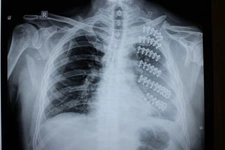

1. KalpKalp, göğüs kafesinin ortasında, kaburga kemiklerinin hemen altında yer alır. Kalp, vücudun kan pompalama işlevini yerine getirir ve dolayısıyla hayati bir organdır. Kaburga kemikleri, kalbi dış etkenlerden koruyarak, onun sağlıklı bir şekilde çalışmasını destekler. 2. AkciğerlerAkciğerler, kaburga kemiklerinin her iki yanında yer alan, solunum sisteminin en önemli parçalarından biridir. Kaburga kemikleri, akciğerleri korurken, aynı zamanda onların genişlemesini ve daralmasını sağlayan bir yapı oluşturur. Akciğerlerin sağlığı, genel sağlık durumu için kritik öneme sahiptir. 3. TrakeaTrakea, hava yollarını oluşturan tüp şeklindeki bir yapıdır ve akciğerlere hava ileten bir kanal vazifesi görür. Trakea, kaburgaların arasında yer aldığından, hava akışını sağlarken bu alandaki diğer organlarla etkileşim içerisindedir. 4. ÖzofagusÖzofagus, yiyecekleri ağızdan mideye ileten boru şeklindeki bir yapıdır. Kaburga kemiklerinin hemen arkasında yer alır ve bu sayede besinlerin mideye taşınmasında önemli bir rol oynar. 5. DiyaframDiyafram, göğüs boşluğuyla karın boşluğunu ayıran kaslı bir yapıdır. Kaburga kemiklerinin alt kısmında yer alarak, solunum sırasında akciğerlerin genişlemesine yardımcı olur. 6. Medastinum OrganlarıMedastinum, göğüs kafesinin ortasında yer alan ve birçok önemli organı içeren bir boşluktur. Thymus, büyük damarlar ve lenf düğümleri gibi organlar bu alanda bulunur. Kaburga kemikleri, bu organların korunmasında önemli bir rol oynar. SonuçKaburga kemikleri, vücut için hayati öneme sahip birçok organı koruyan önemli bir yapıdır. Kalp, akciğerler, trakea, özofagus, diyafram ve medastinum organları, bu yapı içerisinde yer alarak, insan sağlığının sürdürülmesinde kritik bir rol oynar. Kaburga kemiklerinin sağlıklı bir yapıya sahip olması, bu organların düzgün bir şekilde çalışmasını destekler. Ekstra BilgilerKaburga kemikleri, çeşitli sağlık sorunları ve yaralanmalara karşı hassas bir yapıdadır. Kaburga kırıkları, ciddi yaralanmalara neden olabilir ve bu durum, yukarıda bahsedilen organların işlevselliğini etkileyebilir. Dolayısıyla, göğüs kafesi yaralanmalarının önlenmesi ve tedavisi, sağlık açısından büyük önem taşır. |

Akciğerler de kaburgalar tarafından korunmaktadır ve bu durum, solunum sağlığı açısından son derece önemlidir. Kaburgalar, akciğerlerin genişlemesi ve daralması sırasında hareket etmelerine olanak tanırken, aynı zamanda onları dış darbelerden korur. Sağlıklı akciğerler, genel sağlık durumunun bir göstergesi olduğundan, kaburga kemiklerinin durumu da bu bağlamda önem taşır.

Diyafram, solunumda kritik bir rol oynamaktadır. Kaburga kemiklerinin sağlığı, diyaframın düzgün çalışmasını ve böylece solunumun etkili bir şekilde gerçekleşmesini sağlar. Diyaframın kasılması ve gevşemesi, akciğerlerin havayı alıp vermesi üzerinde doğrudan etkilidir.

Mediastinum, kalp, trakea ve özofagus gibi önemli organların bulunduğu bir alandır. Kaburga kemikleri bu bölgedeki organların korunmasında da önemli bir rol oynar. Bu nedenle, kaburgalarda yaşanacak herhangi bir sorun, bu organların işlevselliğini olumsuz etkileyebilir.

Kaburga kemiklerinde bir sorun yaşandığında, bu durum kalp ve akciğer gibi hayati organların işlevselliğini etkileyebilir. Örneğin, kaburga kırıkları veya çıkıkları, nefes almayı zorlaştırabilir, bu da akciğerlerin oksijen alımını azaltır. Ayrıca, kalbin düzgün çalışmasını da tehdit edebilir. Dolayısıyla, kaburga kemiklerinin sağlığı, tüm bu organların dengeli bir şekilde çalışması için son derece önemlidir.